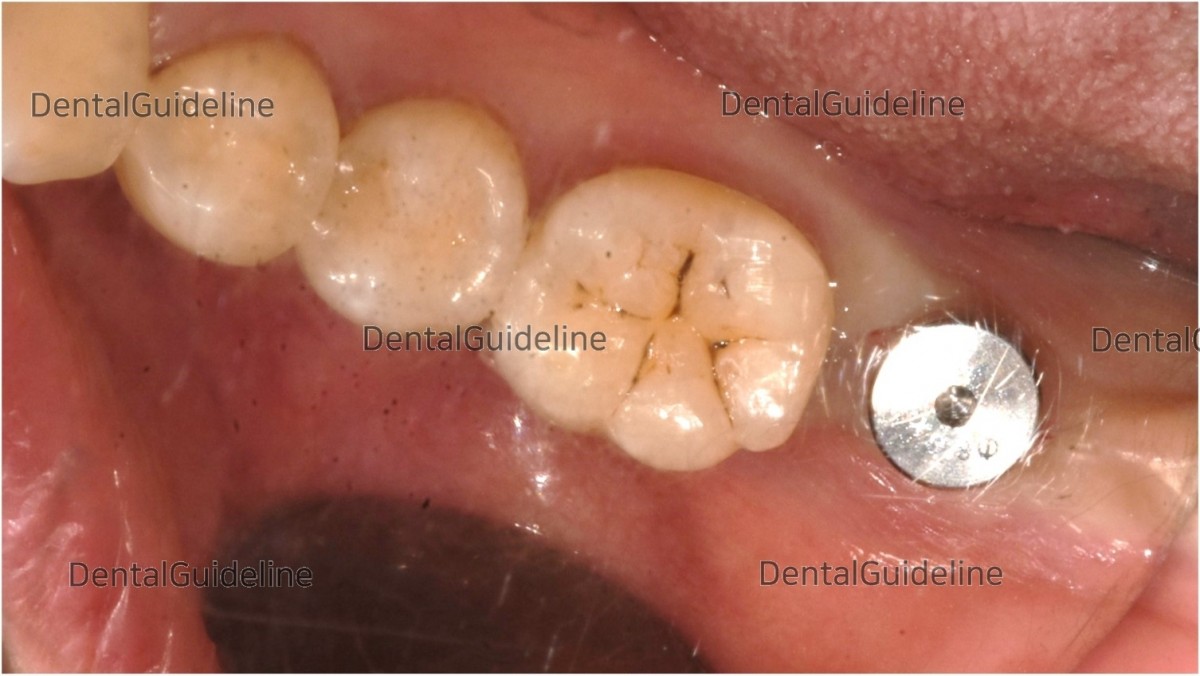

1. Intraoral view before surgery

9. Post-op 10week, intra-oral photo on the day of uncovery.

12. ISQ measurement (10 weeks after the placement of implant). Photos showed that ISQ values were good enough for loading.